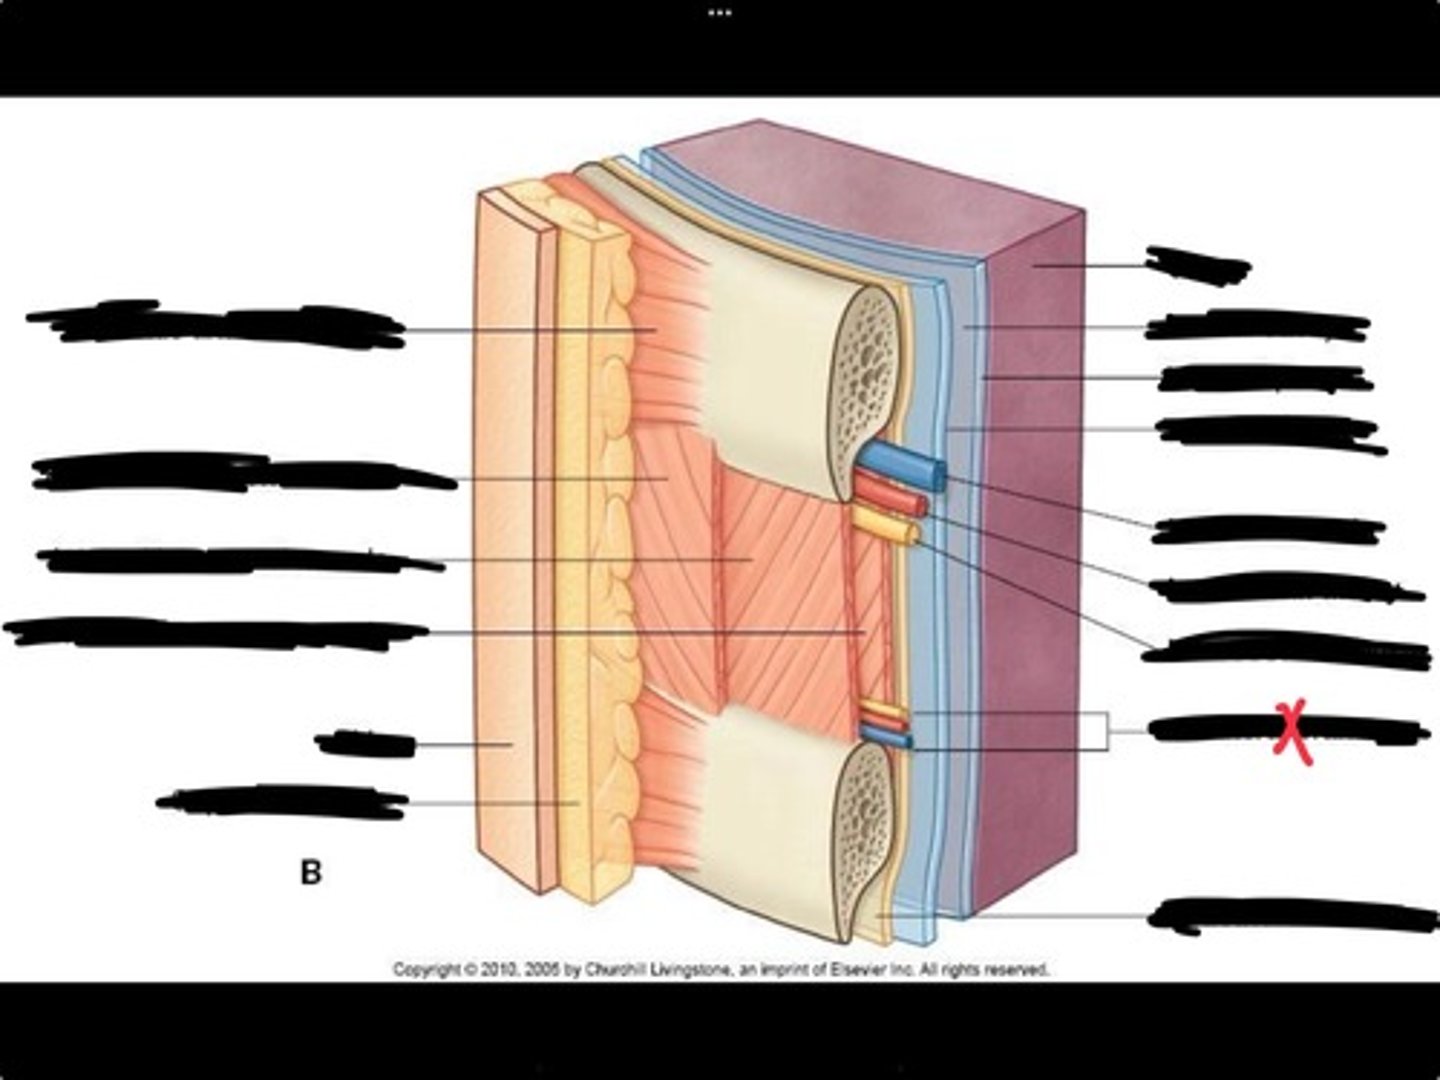

Innermost intercostal muscle

Skin

Internal intercostal muscle

External intercostal muscle

Serratus anterior muscle

Lung

Pleural cavity

Visceral pleura

Parietal cavity

Intercostal vein

Intercostal artery

Collateral branches

Intercostal nerve

Endothoracic fascia